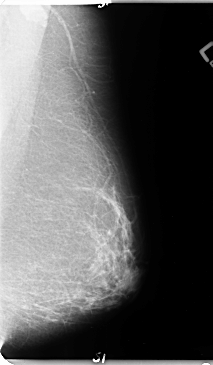

B_3124_1.LEFT_MLO

LEFT_MLO LINES 4744 PIXELS_PER_LINE 2760 BITS_PER_PIXEL 12 RESOLUTION 50 NON_OVERLAY